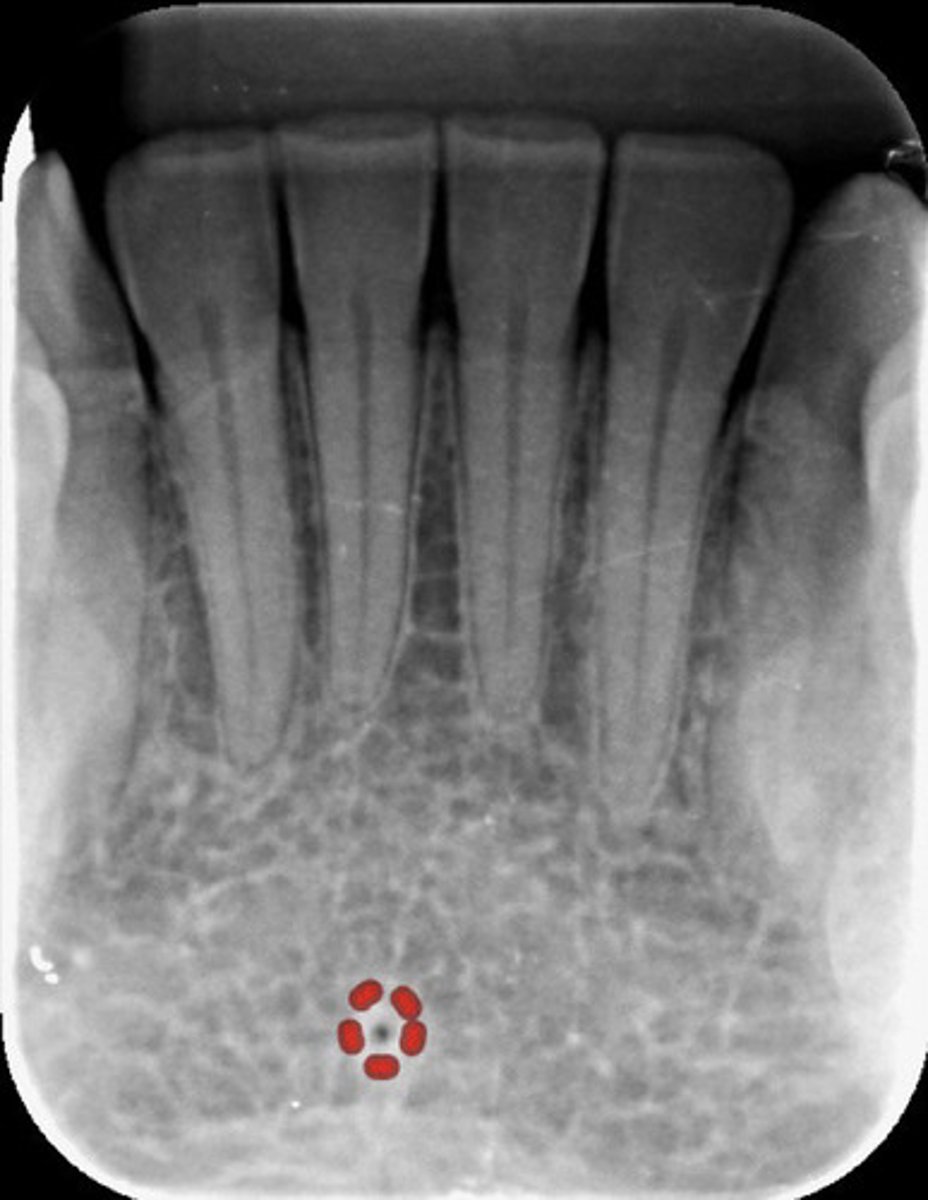

What is the lingual foramen?

What does the lingual foramen look like radiographically?

INFOrmation on lingual foramen

radiolucent & in the mandible srrouned on genial tubercules

What are genial tubercles?

information genial tubercules

inferior to mandibular incisors & radiopaque

What do genial tubercles look like radiographically?